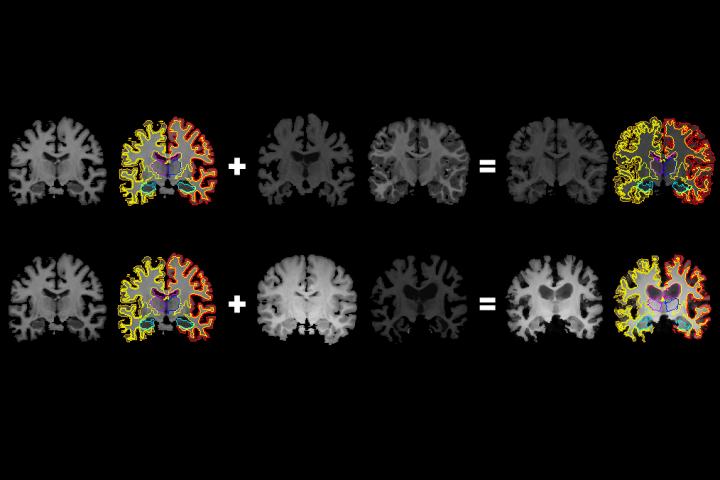

image: MIT researchers have developed a system that gleans far more labeled training data from unlabeled data, which could help machine-learning models better detect structural patterns in brain scans associated with neurological diseases. The system learns structural and appearance variations in unlabeled scans, and uses that information to shape and mold one labeled scan into thousands of new, distinct labeled scans. view more

In generating a new scan, the system applies a random flow field to the original labeled scan, which shifts around voxels until it structurally matches a real, unlabeled scan. Then, it overlays a random intensity transformation. Finally, the system maps the labels to the new structures, by following how the voxels moved in the flow field. In the end, the synthesized scans closely resemble the real, unlabeled scans -- but with accurate labels.